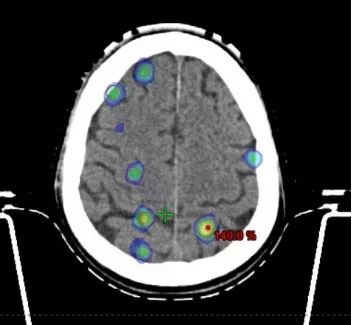

而我院采用的最新的HyperArc技术则是对VMAT技术再一次优化。HyperArc技术几乎适合所有的颅脑肿瘤,特别是在颅内多发肿瘤方面优势更加显著。

HyperArc治疗颅内多发肿瘤,可一次性照射多个肿瘤靶区,同时确保肿瘤受到充分照射的同时,保护正常脑组织

02 自动化流程,一键式操作缩短治疗时间

HyperArc技术让肿瘤治疗流程更加简化。在放疗过程中,放疗技师只需要在操作间一键执行,整个放疗流程就能自动进行。该自动化流程能够实现一次性同时“打击”十几个肿瘤病灶,无需进入治疗室重新对患者进行摆位或者手动移床(在以往的治疗中,每个患者位置的改变,都需要人工进行摆位和治疗前的摆位验证,单次治疗需要耗费更多的时间),缩短了治疗的总时间。